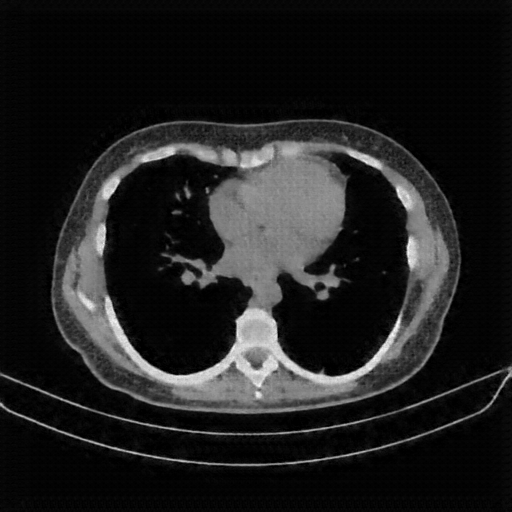

Image Grid

4Γ—3 grid: Rows show different image types (Original NATIVE, Reconstructed NATIVE, Original VENOUS, Generated VENOUS), Columns show windowing techniques (No Window, Lung Window, Mediastinum Window)

Lung window (WL -600, WW 1500 β†’ Low βˆ’1350, High +150)

Reconstructed NATIVE CT scan (cycle consistency)

Original VENOUS CT scan

Generated VENOUS CT scan (A→B translation)